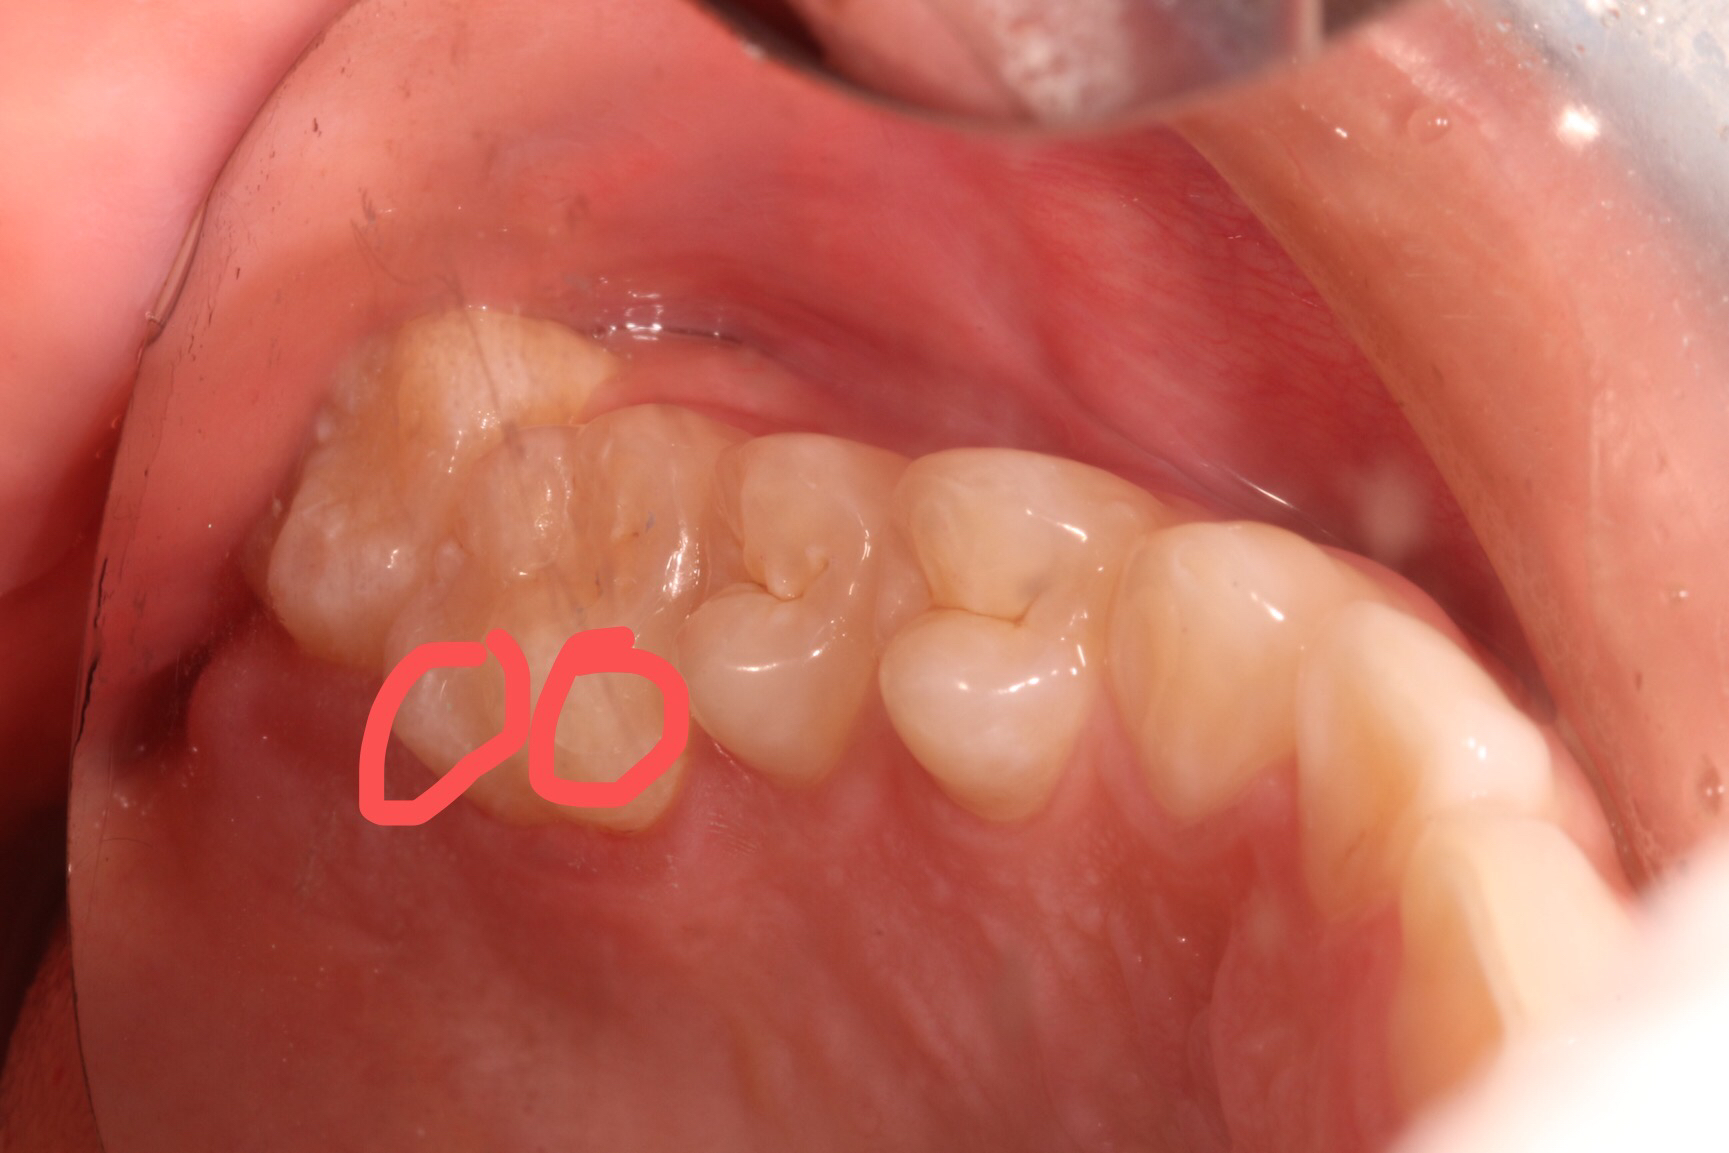

铒激光微创补牙 :这样的窝沟点隙,有点龋坏,用球钻去除,破坏好牙有点多,不忍心;有没有更好的办法呢,用铒激光去除龋坏,专心、专业去除坏牙,还有杀菌、消毒、脱敏的功效,减少补牙术后敏感症状及继发龋坏的发生,另外还有酸蚀的作用,减少了化学药物的影响;没有窝轮机的振动,非常轻柔的啪啪的响声,能够高效、微创去除龋坏,高科技一铒激光微创补牙,您值得拥有!